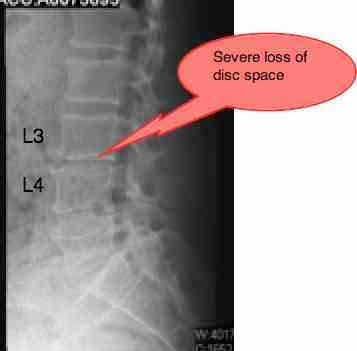

As expected, he has marked loss of disc space at L3-L4, and the oblique reveals degenerate facets at two levels: L1-L2 (hence the groin pain) and L3-L4 (anterior thigh pain).

No x-rays had been taken. Probable loss of L2 L3 disc space and degenerative arthritis in the L2 L3 facet right, possibly with a capsular invagination or cyst, and possible antero or retro lysthesis.

Mr R almost certainly has fairly severe loss of the foraminal space, from a previous injury causing loss of the disc space. The front (inferior) facet then becomes degenerate, often forming a sharp scimitar that threatens the nerve root. It's not impossible that there is a capsular cyst, seen only on MRI, threatening the nerve root. I really should have ordered at least an X-ray and probably an MRI.